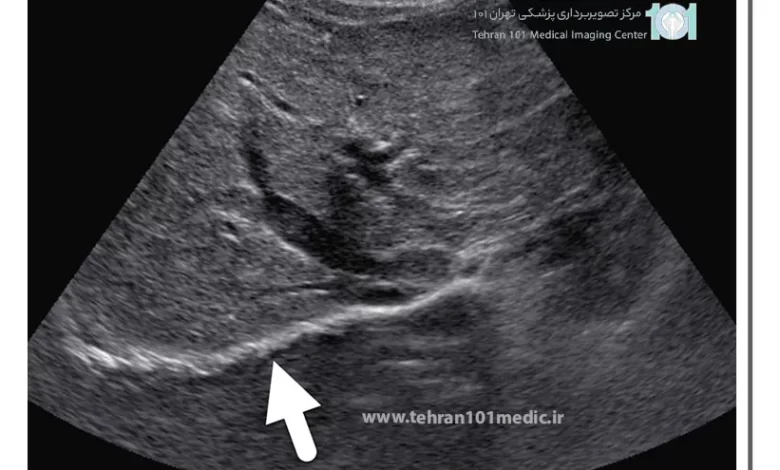

سونوگرافی یا اولتراسوند نوعی آزمایش تصویربرداری تشخیصی غیرتهاجمی بوده که در آن از امواج صوتی با فرکانس بالا استفاده میشود. تصاویری که از طریق سونوگرافی بر روی صفحه مانیتور دیده میشوند به صورت زنده بوده که با حرکت پروب به اطراف میتوان ناحیه مورد نظر را از بخشهای مختلف مورد بررسی قرار داد. از سونوگرافی برای مشاهده بخشهای مختلف بدن استفاده میشود که میتوان از آن برای دیدن چگونگی کارکرد کبد نیز استفاده کرد.

برای تشخیص و درمان بیماریهای مرتبط با کبد میبایست به متخصص گوارش و فوق تخصص کبد مراجعه کرد که ممکن است پزشک تقاضای سونوگرافی کبد را داشته باشد. هنگامی که امواج فرا صوتی تولید شده از پروب از بدن عبور کرده و به کبد میرسد، با وضوح کامل تصاویر بر روی مانتیور دیده میشود که از آن عکس انداخته شده و در صورت لزومی فیلم تهیه میشود. بیمار با در دست داشتن نتیجه آزمایش میتواند به پزشک مراجعه کرده تا علاوه بر تشخیص دقیق، تحت درمان قرار گیرد.

سونوگرافی تصاویری از آناتومی و ناهنجاریهای کبد را نشان میدهد. به کمک سونوگرافی میتوان موارد زیر را تشخیص داد:

- تودههای بدخیم: در کبد ممکن است تودههایی وجود داشته باشد که بدخیم بوده و احتمال دارد از نوع ندول، کلسیفیکاسیون و بافت نواری شکل باشد. تودههای بدخیم حاوی سلول و دارای جریان خون ممکن است سرطانی باشند که از طریق سونوگرافی کبد قابل تشخیص است.

- تودههای خوش خیم: کیستیک و تودههایی وجود دارند که پر از مایع بوده اما بی خطر هستند. سونوگرافی با کنتراست از جدیدترین روشها برای تشخیص بیماریهای مرتبط با کبد است. در این حالت برای انجام سونوگرافی به داخل ورید ماده حاجب ترزیق میشود تا کیفیت و وضوح تصاویر سونوگرافی کبد بالا رود.

سونوگرافی شکمی: این روش اولین گام برای تشخیص کبد چرب است و به ارزیابی اندازه کبد و تشخیص افزایش حجم آن کمک میکند. الاستوگرافی، نوعی سونوگرافی پیشرفته، میتواند سختی بافت کبد و وجود فیبروز یا زخم را معین کند.